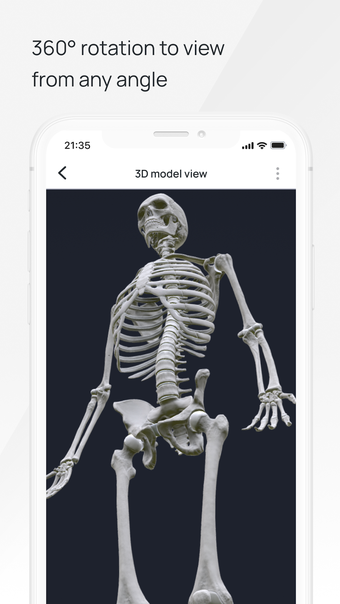

In this atlas of human pathologies you can learn about diseases, their causes, symptoms, and treatment. It contains all the essential information about the anatomy of the human body and its organs. You will be able to study diseases and their causes from an anatomy point of view. It contains information about diseases, their symptoms, and their treatment. In addition, you will be able to view 3D models of all the important organs of the human body.

VOKA Pathology 3D is an educational tool for medical students, lecturers, and physicians. It can help you learn about human anatomy and pathology.